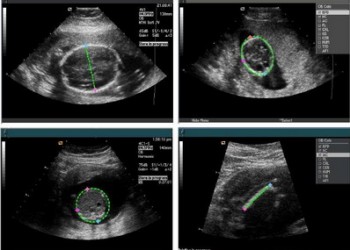

Biometria fetală

Biometria fetala consta în aprecierea ecografica a unor parametri ai produsului de conceptie.

Iată care sunt principalii indici de biometrie fetală:

• DMS (diametrul mediu al sacului) = reprezintă media aritmetică a dimensiunilor craniocaudală, transversală și anteroposterioară a sacului gestațional și este utilizată pentru aprecierea vârstei gestaționale până la 5-6 săptămâni de amenoree; valoarea sa este de 2-3 mm la 4 săptămâni, 5 mm la 5 săptămâni și 15 mm la 6 săptămâni

• CRL (crown-rump length) = lungimea cap-șezut, este cel mai bun parametru care estimează vârsta gestațională în primul trimestru (după săptămâna 13, fătul se curbează și aprecierea vârstei gestaționale se face pe baza diametrului biparietal, BPD)

• BPD (biparietal diameter) = diametrul biparietal, este parametrul cu cea mai bună acuratețe în stabilirea vârstei gestaționale în trimestrul 2

• AC (abdominal circumference) = circumferința abdominală, prezintă o acuratețe maximă în corelarea cu vârsta gestațională între săptămânile 26-31

• FL (femoral length) = lungimea femurului

• HC (head circumference) = circumferința craniană

În momentul efectuării măsurătorilor, valorile sunt automat calculate de aparatul de ecografie și după compararea cu nomograme, afișează vârsta gestațională corespunzătoare valorii determinate.